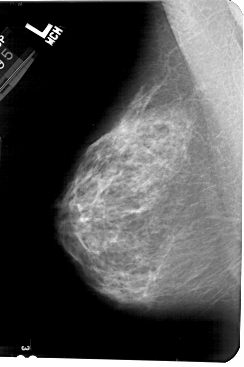

A_1569_1.RIGHT_MLO

LEFT_MLO LINES 5491 PIXELS_PER_LINE 3646 BITS_PER_PIXEL 12 RESOLUTION 43.5 NON_OVERLAY